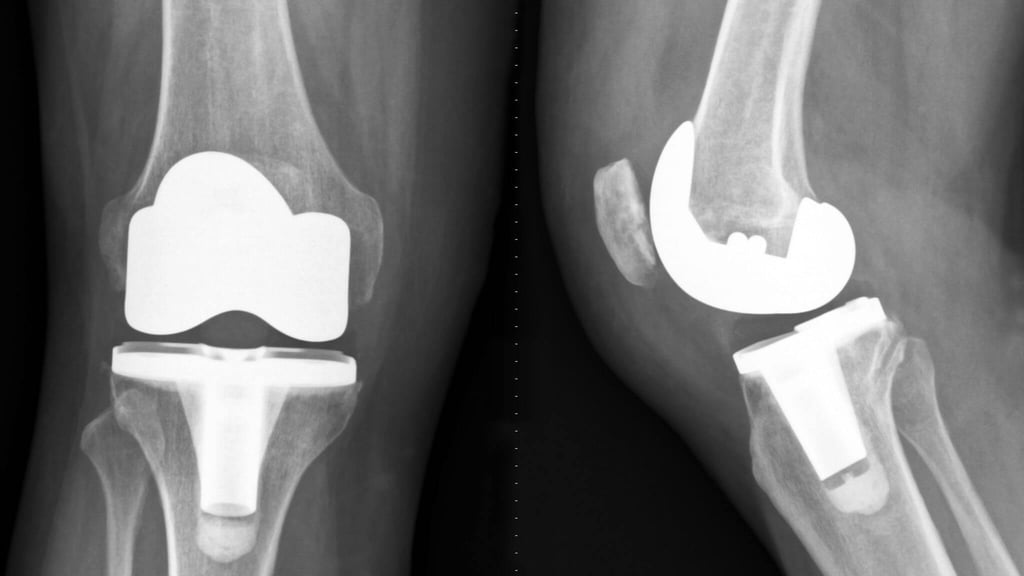

Advanced joint reconstruction using durable hip and knee replacement technology.

Reconstruction